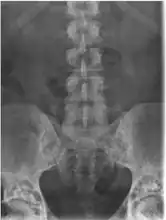

Osteopoikilosis

Note thickened sclerotic cortical bone